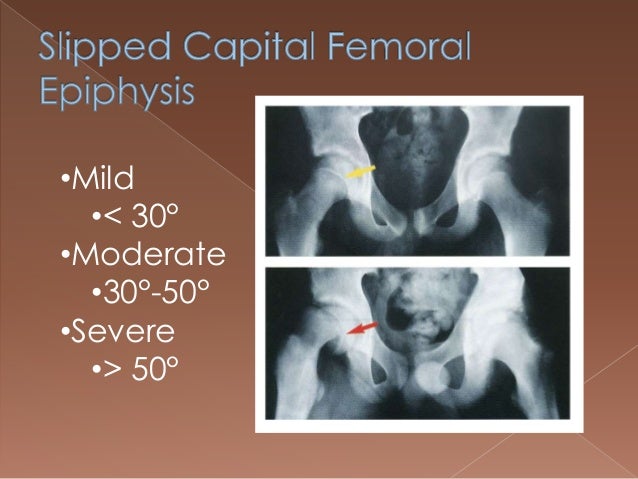

Slipped Capital Femoral Epiphysis

www.slideshare.net

www.slideshare.net

epiphysis slipped femoral